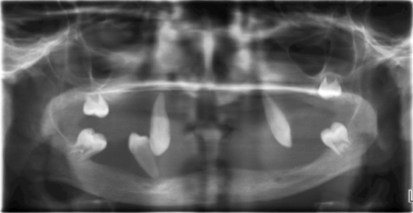

Physical examination revealed symmetrical, well demarcated, yellow keratotic plaques on the skin of the palms and soles, which extended to the dorsal surface of the finger joints and also over the dorsal surface of the feet. These keratotic plaques on the skin were dry, scaly and rough on palpation (Figure 1). On intra-oral examination, it was found that except for the canine and the erupting lower third molar, all the other permanent tooth including the left lower canine were missing. (Figure 2). Mobility was present in all permanent canines that were present. The gingiva in relation to the existing permanent tooth was red, edematous with marked clinical attachment loss. Despite the severity of the periodontal involvement, no visible local factors were found. The mucosa of the edentulous area near the periodontally involved teeth was normal. The dental panoramic radiograph showed severe alveolar bone loss in relation to the existing permanent teeth up to the apical third of the roots, giving the teeth a 'floating in air' appearance (Figure 3). The lateral view of the skull radiograph showed no evidence of intracranial calcification. Since the prognosis was very poor for the remaining permanent teeth, complete extraction of the mobile teeth, with subsequent prosthetic rehabilitation was advised.

Figure 2: Oral cavity with loss of several permanent teeth in the male patient (case 1).

Figure 3: The dental radiograph showing severe alveolar bone loss giving the teeth "floating in air" appearance in the male patient (case 1).